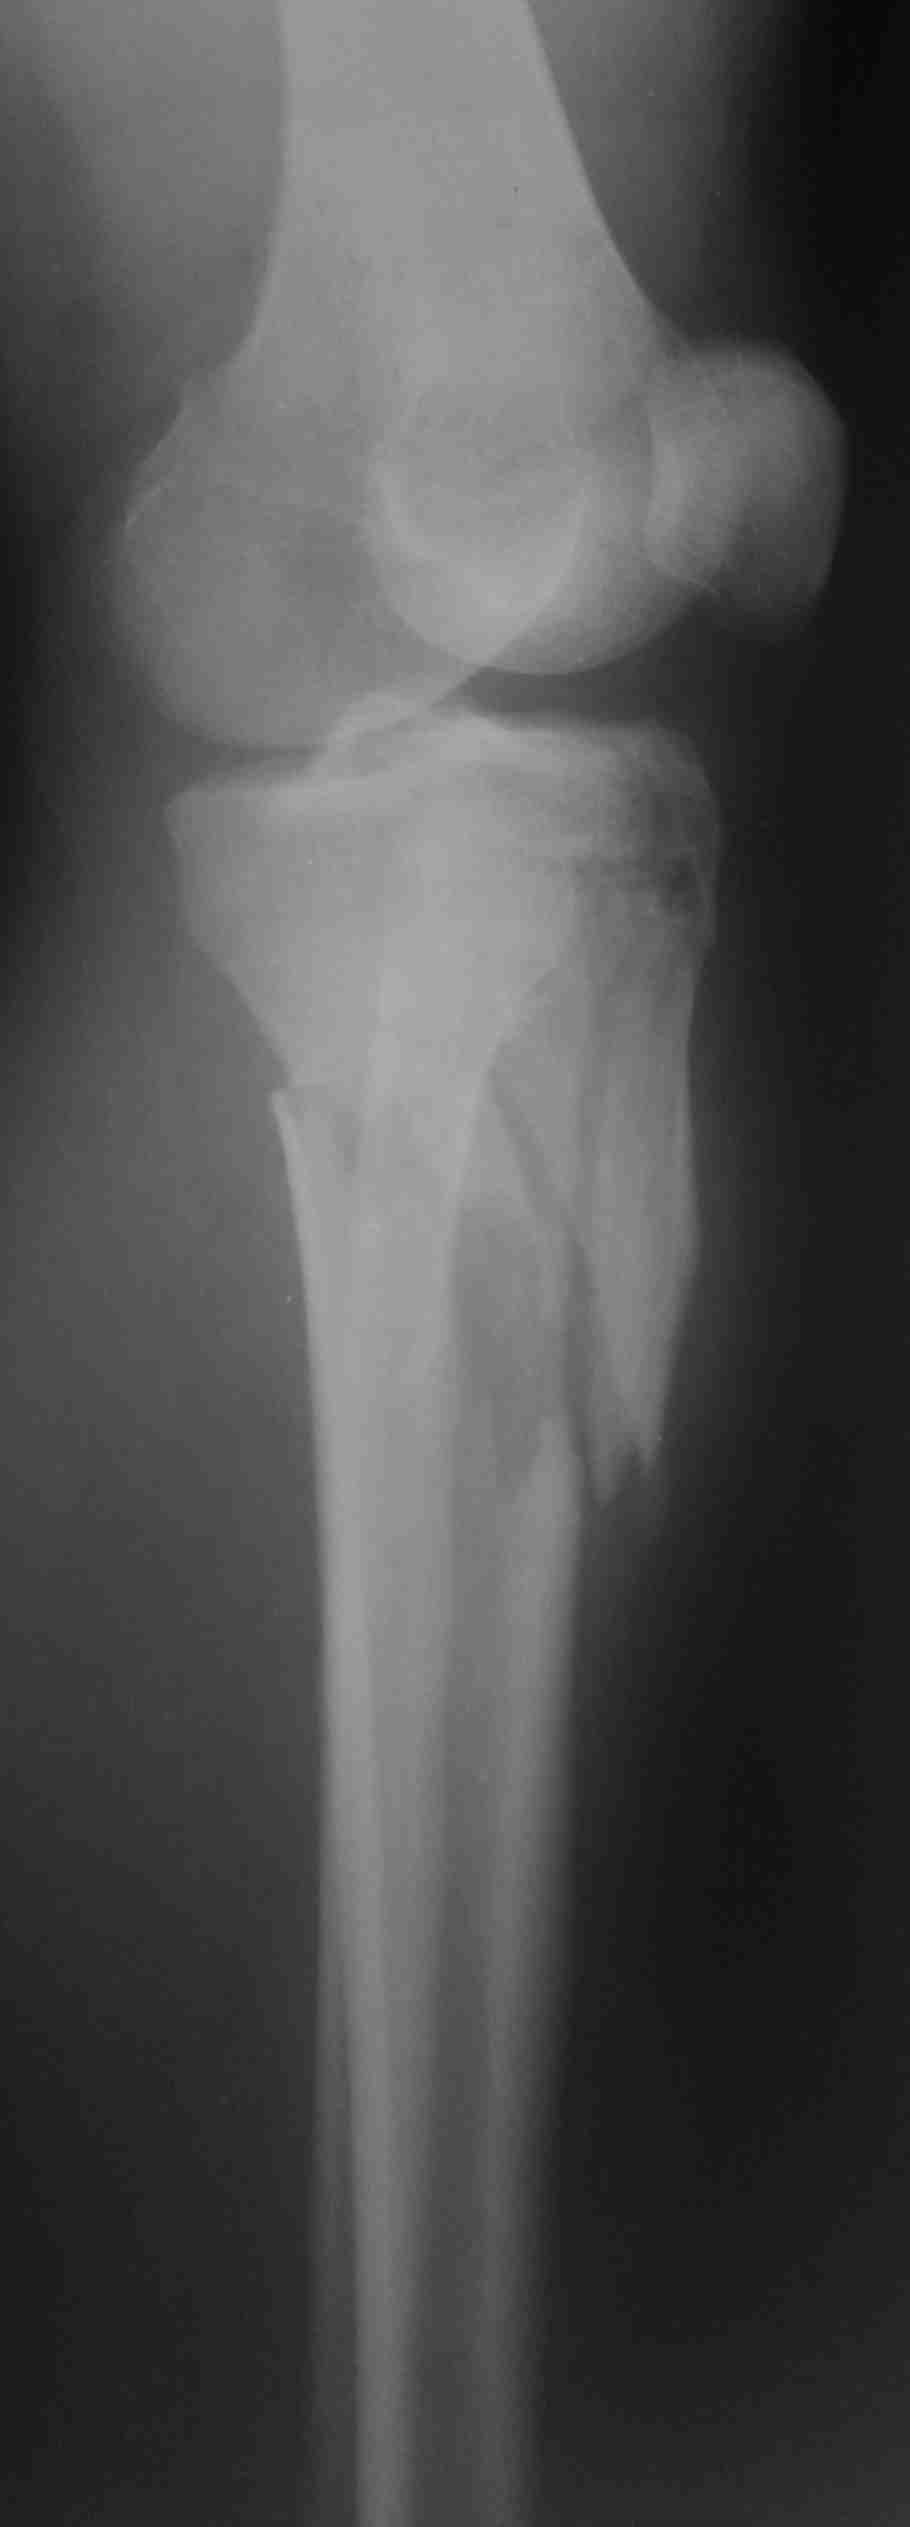

Похожий случай, вчера прооперировали. Непрямая репозиция, малоинвазивный остеосинтез без обнажения зоны перелома.